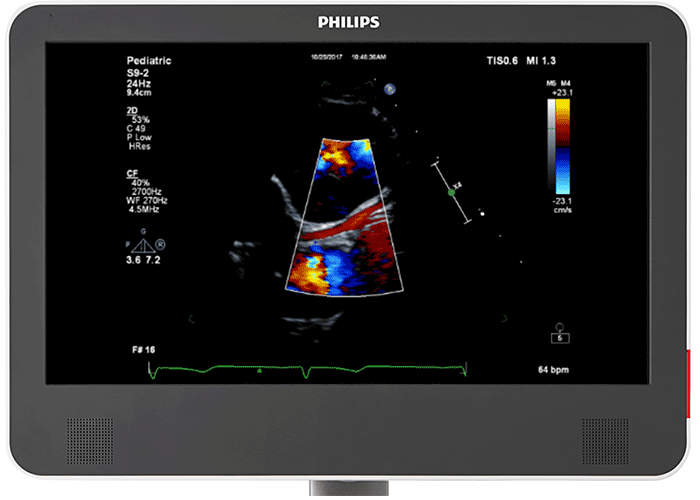

The Philips EPIQ CVx builds on a long tradition of innovative firsts in paediatric cardiology with the addition of many dedicated paediatric cardiology innovations like the Philips S9-2 transducer - a dedicated paediatric PureWave 2D TTE transducer - as well as a one-button coronary sub-mode, and an innovative 3D photo-realistic image rendering. The EPIQ CVx boasts a wide range of 2D and 3D transthoracic and transesophageal transducers for use from foetal to neonates to paediatrics to an adult congenital patient population.

PureWave transducer built for paediatrics cardiology The Philips PureWave S9-2 transducer allows you to visualise extraordinary levels of detail and contrast resolution with exceptional penetration at higher frequencies through ultra-wide bandwidth and